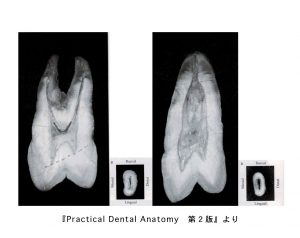

上顎切歯の中身

• 歯の外形を縮小した形を示す。三角形、ロート状、棒状である。

• 根尖側1/3から根尖端に向けて細くなっている。

• 隣接面からみた根管は、唇側面からみた根管より幅広い。

• 根管は根管口から根尖孔までまっすぐとは限らず、根尖付近で少し湾曲している。

下顎切歯の中身

• 歯の外形を縮小した形を示す。細い三角形、ロート状、棒状を示す

• 中央1/3から根尖に向かって著しく細くなっている。

• 隣接面からみた外形は幅広い紡錘形を示す。根管は根管口から中央1/3まで幅広く、根尖側1/3で細くなっている。

• 根尖孔は根尖端とは限らず、根尖孔からそれたところにも開口する。

• 2根管性が20%存在。